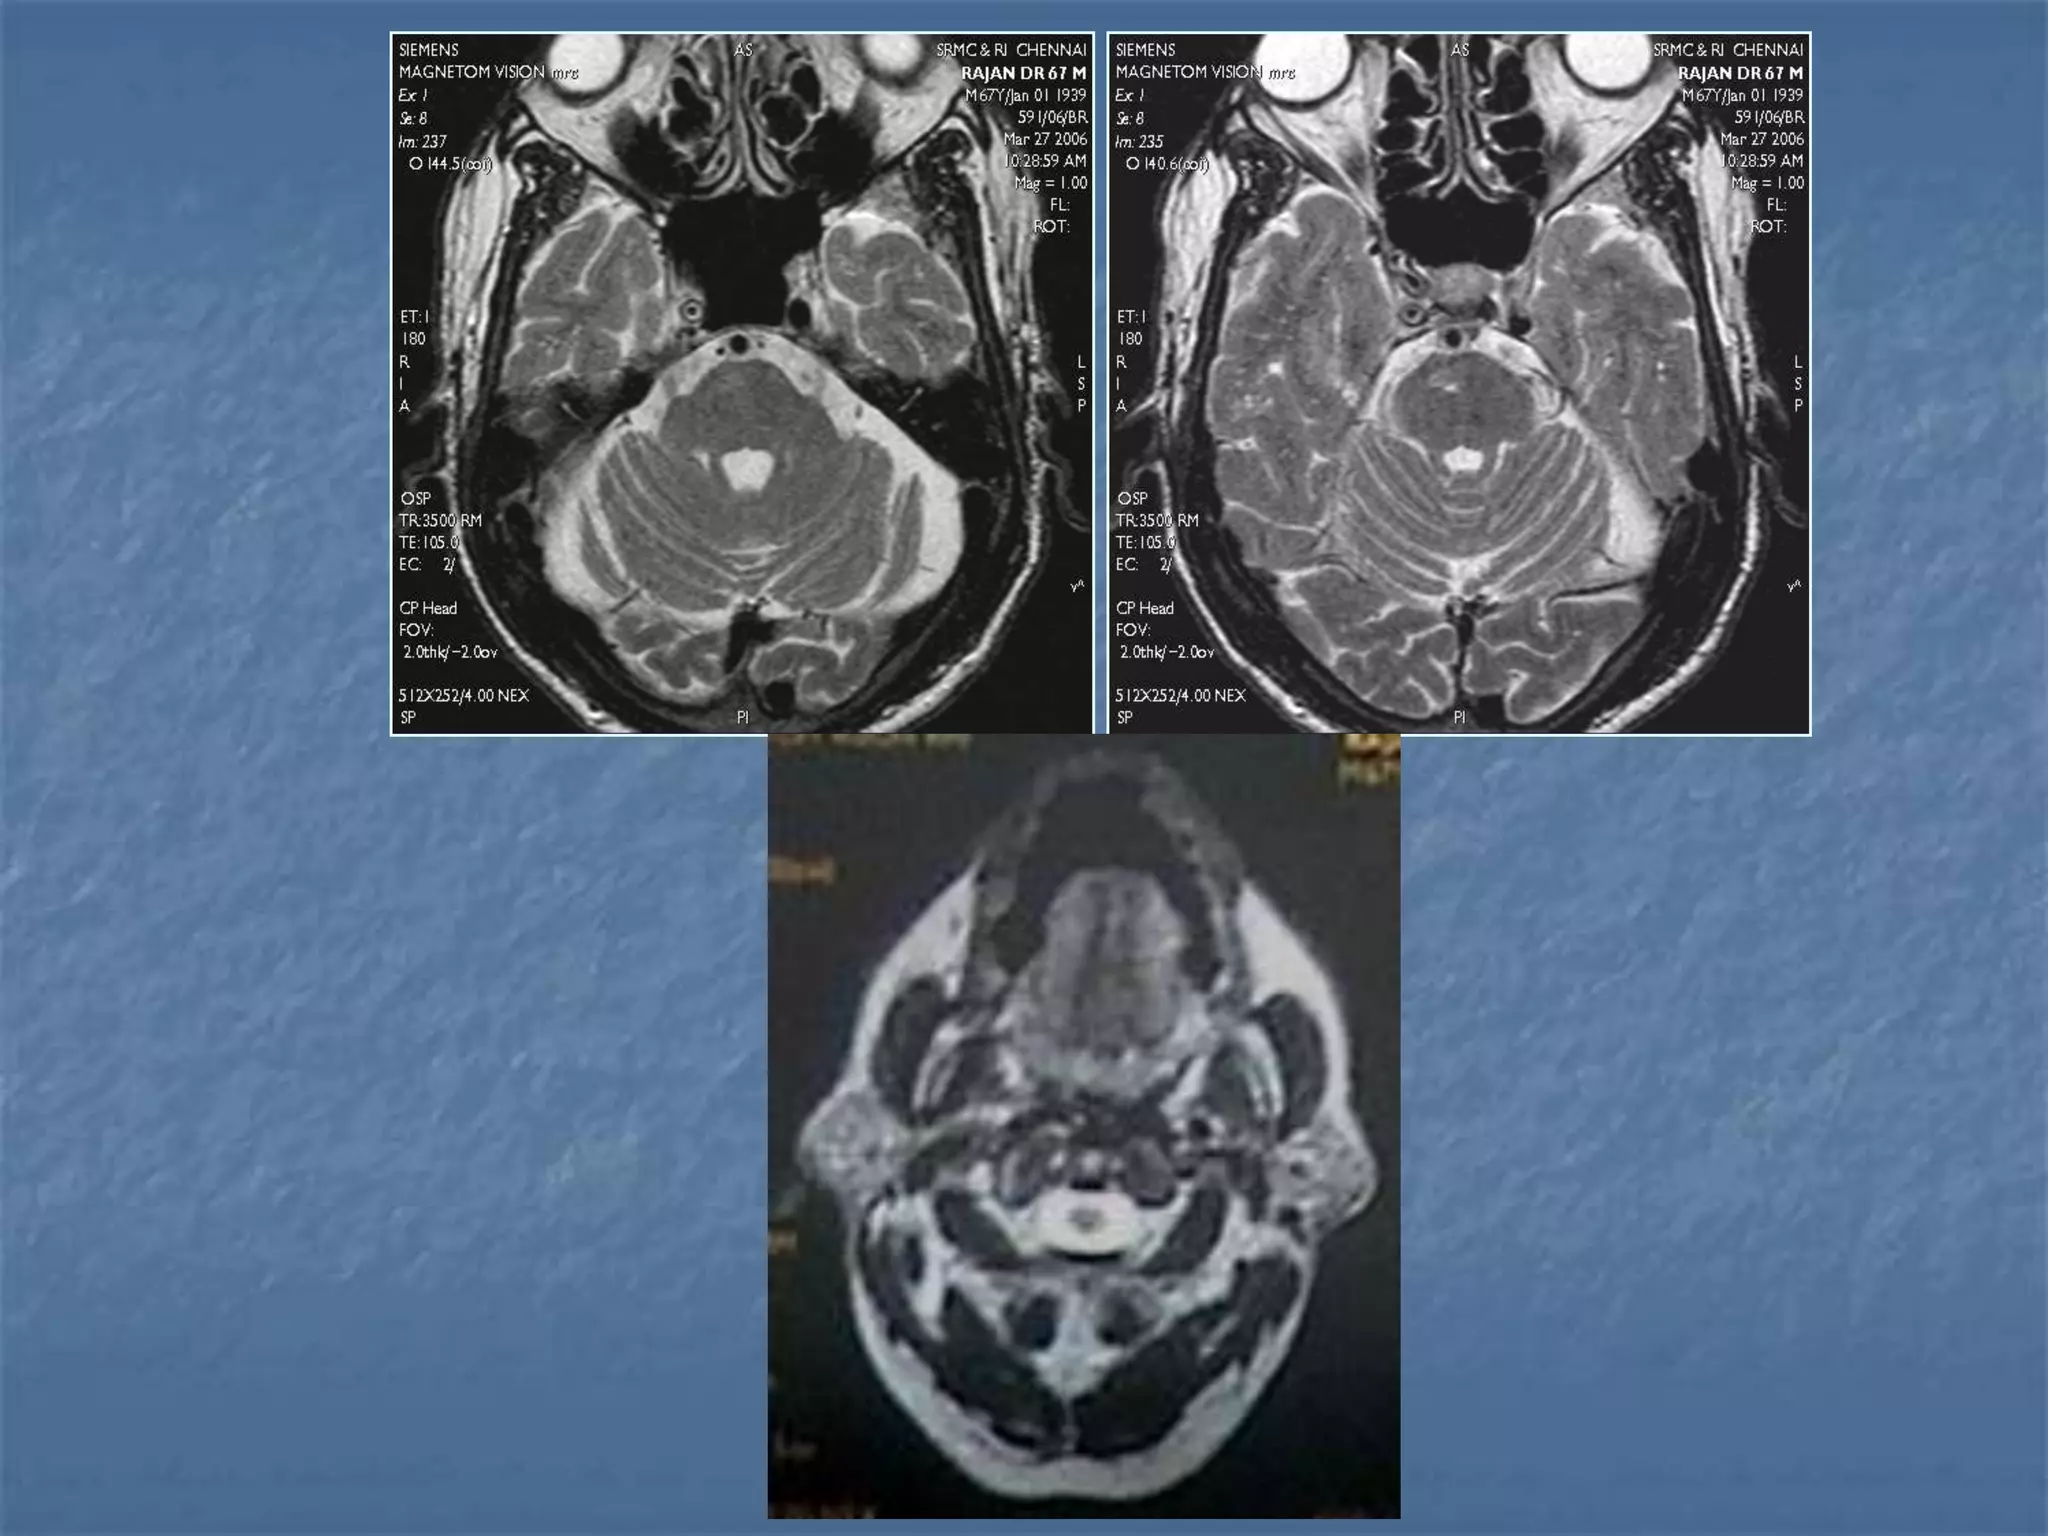

 Hypertensive hemorrhage accounts for

approximately 70-90% of non-traumatic primary

intracerebral hemorrhages. It is commonly due to

vasculopathy involving deep penetrating arteries

of the brain. Hypertensive hemorrhage has a

predilection for deep structures including the

thalamus, pons, cerebellum, and basal ganglia,

particularly the putamen and external capsule.

Thus, it often appears as a high-density

hemorrhage in the region of the basal ganglia.

Blood may extend into the ventricular system.

Intraventricular extension of the hematoma is

associated with a poor prognosis.

Haemorrhagic StrokeEtiology

 Location of hypertensive hemorrhage:

Putamen, external capsule, thalamus, pons,

cerebellum, subcortical white matter